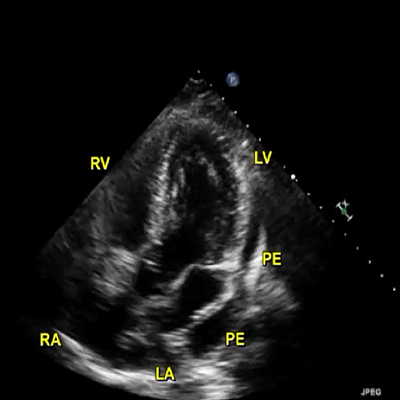

PE: thickened TV

|

543 KB

Large PE

|

950 KB

Large PE. Mild TR

|

915 KB